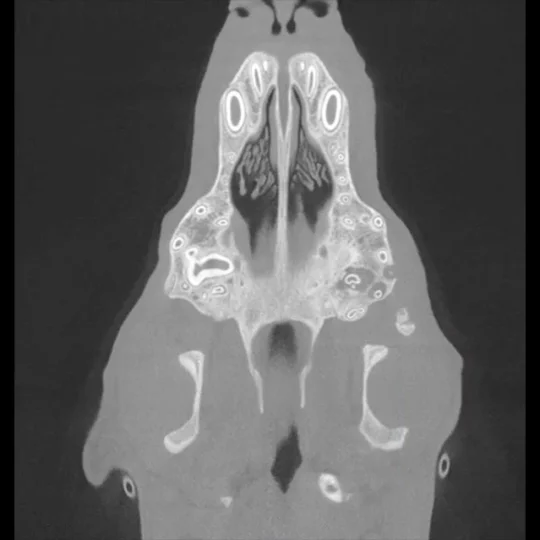

Tomografia komputerowa jest coraz częściej wykorzystywana w diagnostyce stomatologicznej zwierząt, zwłaszcza w przypadkach trudnych, przewlekłych lub wymagających precyzyjnego planowania leczenia. W porównaniu do klasycznych zdjęć RTG, tomografia oferuje znacznie wyższą rozdzielczość i możliwość trójwymiarowej rekonstrukcji struktur kostnych, co pozwala na dokładną ocenę zmian niedostrzegalnych w tradycyjnych badaniach obrazowych.

W szczególności, tomografia komputerowa znajduje zastosowanie w:

Badanie to jest szczególnie przydatne u pacjentów z przewlekłym stanem zapalnym jamy ustnej.